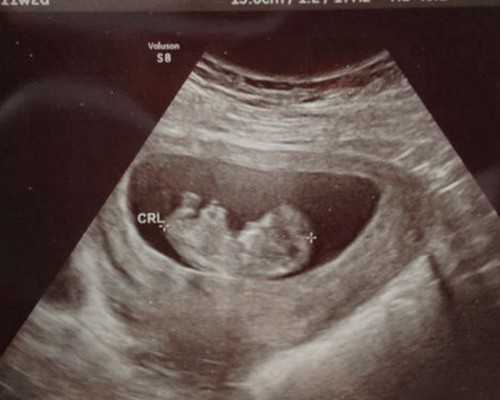

第四步:移植。常规是在取卵后的第三天进行胚胎移植。

第六步:验孕。移植两周后可以进行验孕,判断是否成功着床。